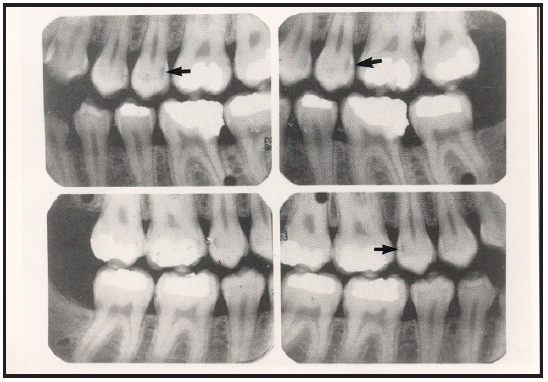

Bitewing examinations were introduced by Dr. Raper in 1925. Bitewing images focus on the clinical crowns of both the maxillary and mandibular teeth. Bitewings do not show the apices of the tooth and cannot be used to diagnose in this area. The greatest value of bitewing radiographic images is the detection of interproximal caries in the early stages of development, before it is clinically apparent. The arrows in Figure 2 indicate areas of interproximal caries. Bitewing images also reveal the size of the pulp chamber and the relative extent to which proximal caries have penetrated.

Tube head position is illustrated in Figure 62, and a sample set of bitewing radiographic images are illustrated in Figure 63.

Figure 2 – Bitewing Images

Figure 2

Figure 63 – Bitewing Series

Figure 63